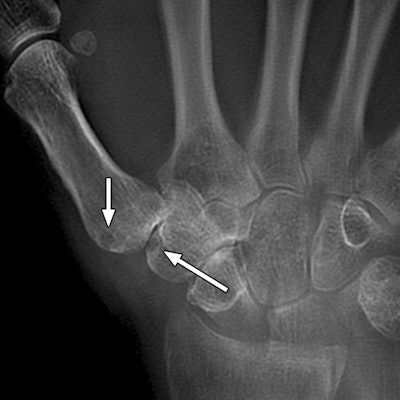

Images are of a 67-year-old man with rheumatoid arthritis. Bone erosion with significant overlapping of bones (arrows) can be difficult to evaluate on radiography (above), compared with tomosynthesis (below and bottom). Images courtesy of AJR.